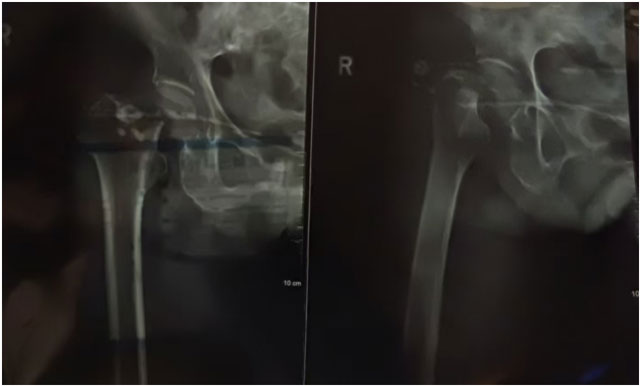

眼看快到百岁生日,杨婆婆却不慎在家中摔倒,导致右侧股骨颈骨折。对于年近百岁的老人,这种骨折被称为“人生最后一次骨折”。家人紧急将她送至西南医科大学附属医院骨科与运动医学中心。

经检查,杨婆婆的身体状况非常复杂。除了严重的右侧股骨颈骨折,她还伴有双侧胸腔积液、肺部感染、心房肥大、三尖瓣返流(重度)、二尖瓣返流(轻度)、心律失常等,这为手术治疗带来了巨大的风险。

在制定了周密的手术方案和应急预案后,骨科团队凭借精湛的技术,成功为杨婆婆实施了“半髋关节置换术”。手术时间短、创伤小、出血少,为术后的快速康复打下了基础。“双侧胸腔闭式引流术+心肺康复”有效缓解了婆婆呼吸困难,控制肺部感染。